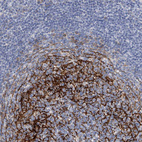

Immunohistochemical staining of human duodenum shows strong cytoplasmic positivity in lymphoid cells.